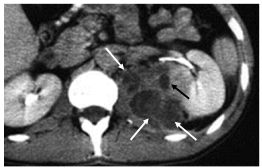

- abcès du rein : collection intrarénale arrondie organisée, avec une coque qui se rehausse après injection et avec une composante centrale purulente de densité liquidienne (figure 26.2), parfois associée à une extension périrénale (figure 26.3) ;

Fig. 26.3. Abcès rénal. Scanner après injection au temps excrétoire.

Abcès par voie hématogène avec petit foyer cortical (flèche noire) associé à une collection liquidienne cloisonnée périrénale (flèches blanches).

Source : CERF, CNEBMN, 2022.